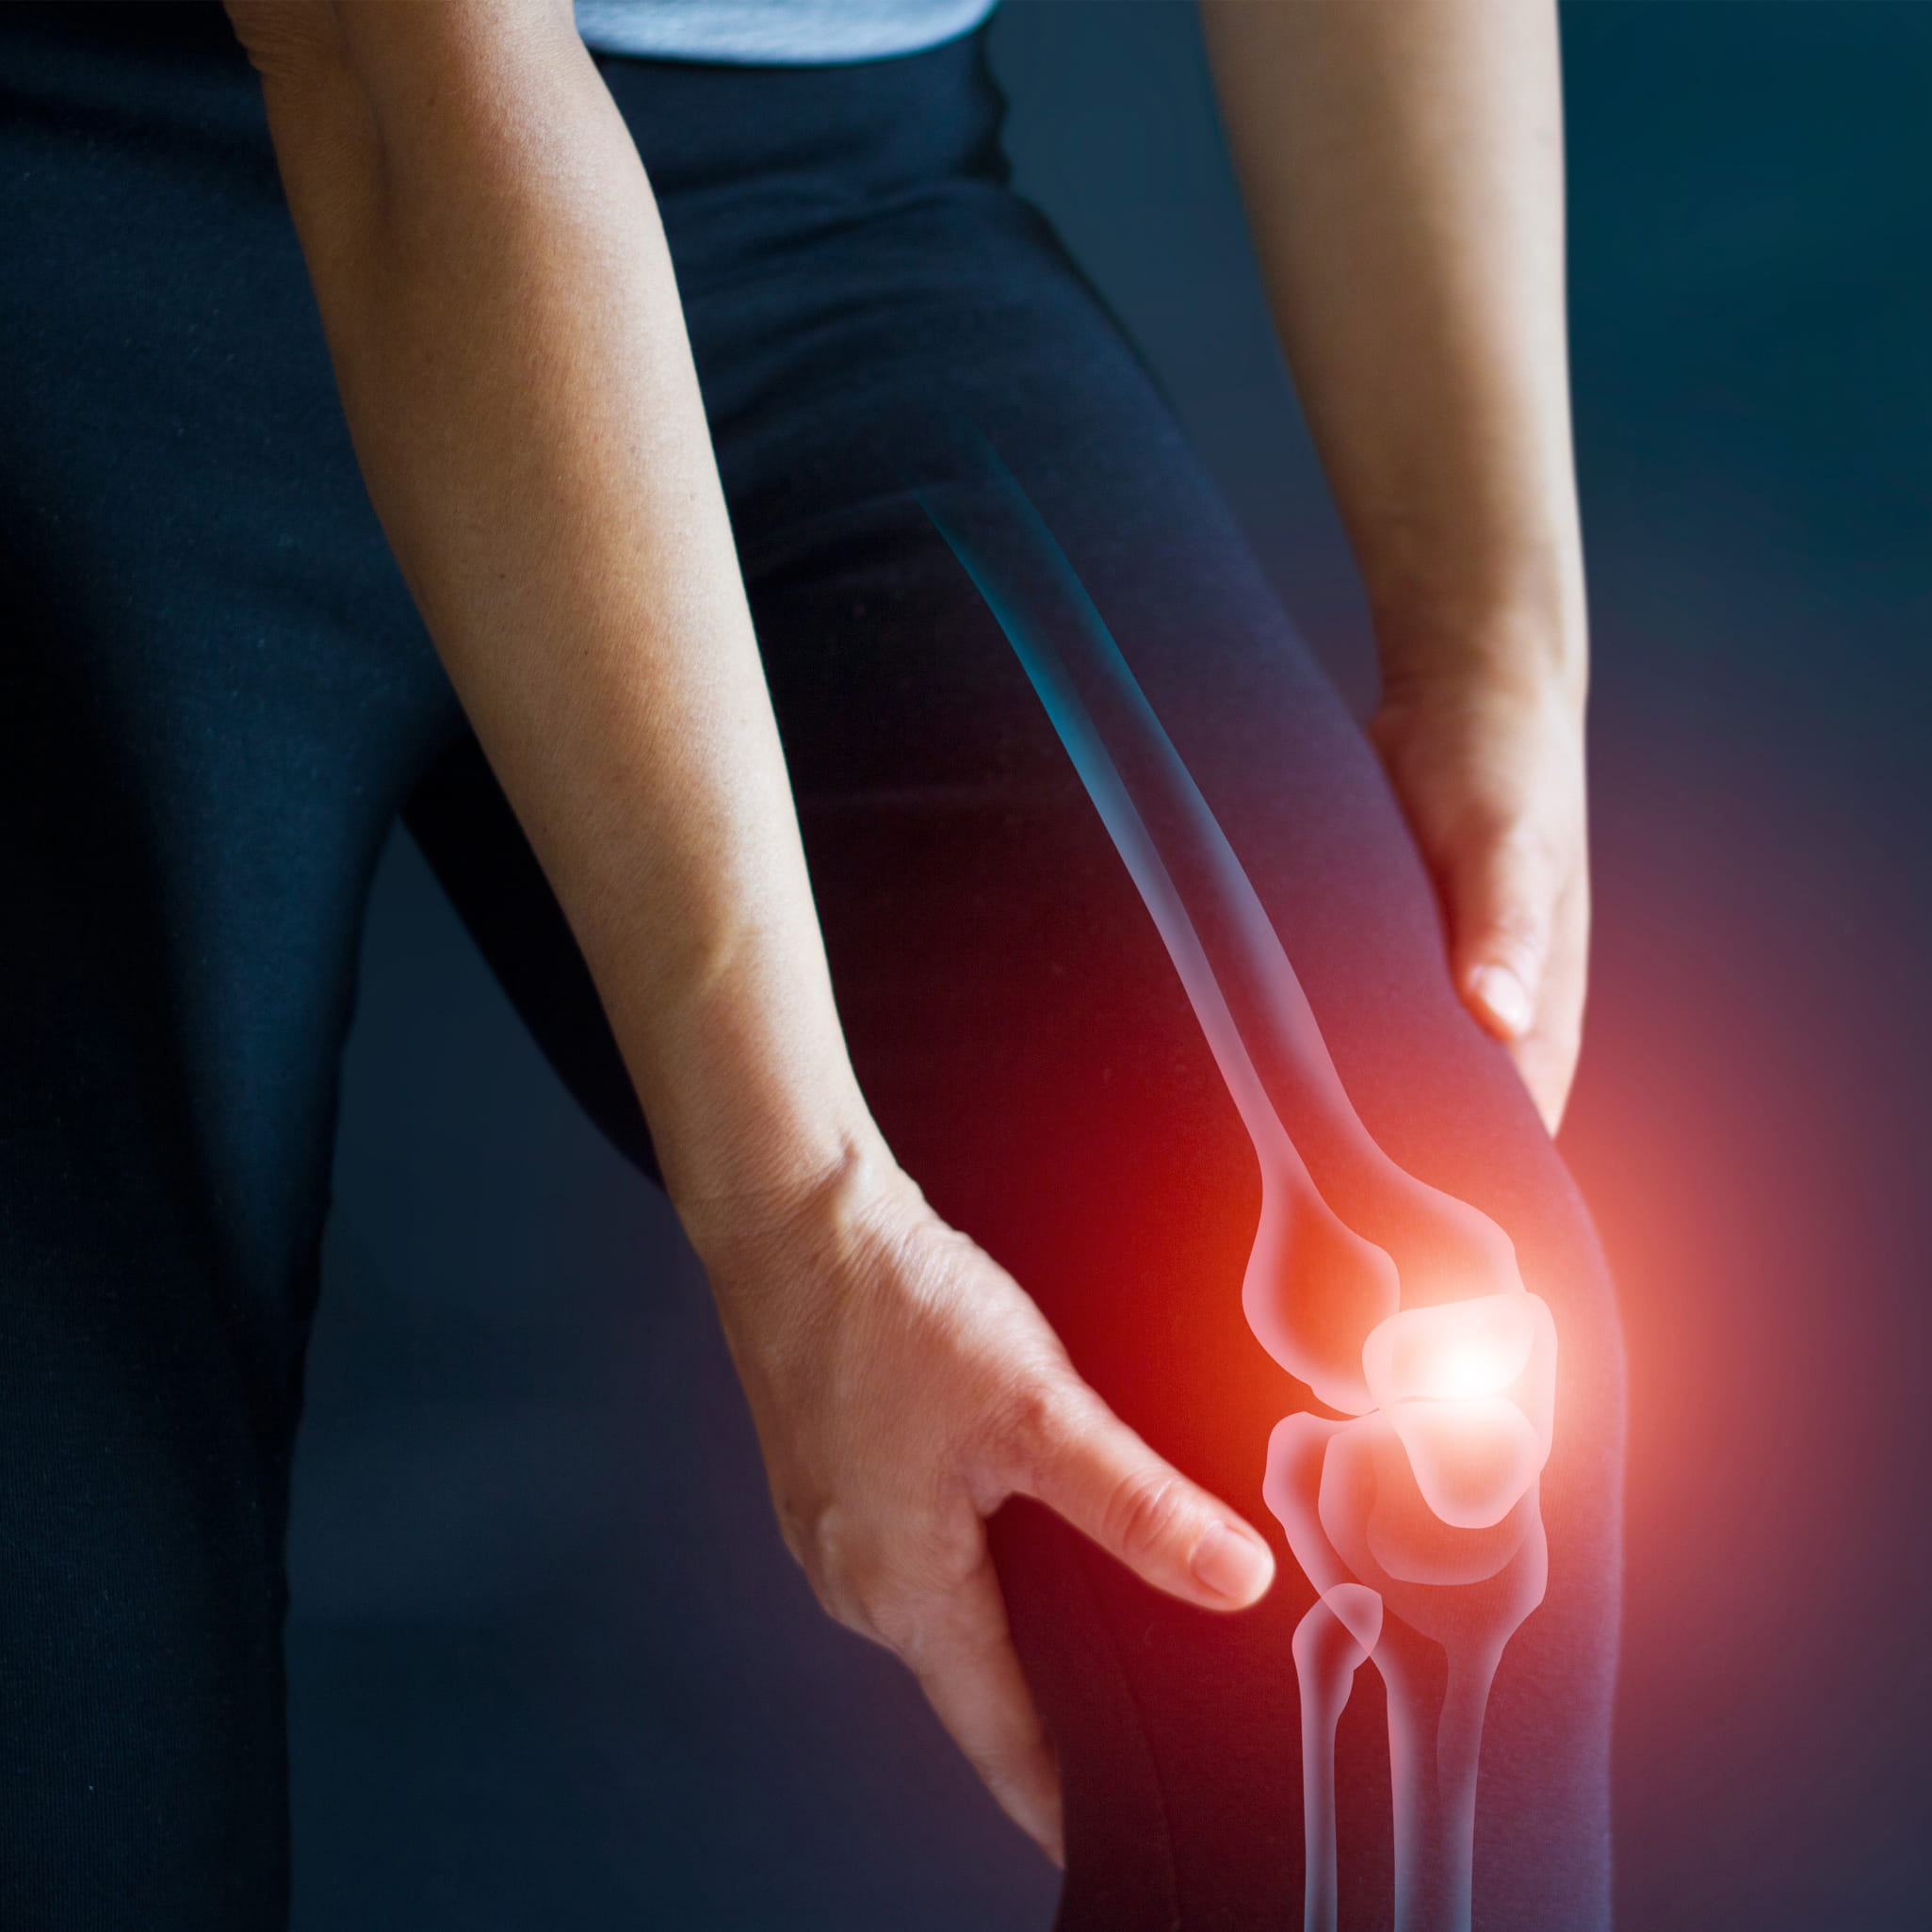

Product id: Pressure under discount knee cap

Patellofemoral Pain Syndrome OrthoInfo AAOS discount, Knee Pain Location Chart The Chelsea Knee Clinic discount, Pain Below The Knee Causes Treatment Of Pain Under The Knee discount, Knee pain MedlinePlus Medical Encyclopedia discount, Patellofemoral Pain Syndrome OrthoInfo AAOS discount, Patella Tendinopathy also known as Jumper s Knee Complete Physio discount, Knee Pain Symptoms and Causes discount, Blog Fitness Physio Newcastle Patellofemoral Pain Syndrome discount, Patellar Tendinopathy NHS Lanarkshire discount, Patellofemoral Pain Syndrome PFPS Treatment in NJ Pain discount, 5 Causes of Sharp Stabbing Pain in the Knee that Comes Goes discount, Acupressure for Knee Pain My Doctor Online discount, Knee Pain Causes Diagnosis and Treatment discount, 5 Things To Know about Knee Injections Washington Orthopaedics discount, Physical Therapy in Burr Ridge Hinsdale for Knee discount, Symptoms of an Acute Patellar Injury Sports health discount, Pain Behind Knee Why it Hurts in Back of or Under your Kneecap discount, Understanding Jumper s Knee Sports health discount, Patellar Tendonitis Jumpers Knee Symptoms Diagnosis Treatment discount, What is Patellar Tendonitis Fit2Function Clinics discount, Knee Pain and Patellofemoral Pain Syndrome HealthyChildren discount, Patellar Tendonitis Jumper s knee Symptoms Causes and Treatment discount, Patellofemoral Pain Syndrome discount, Kneecap Bursitis Orthopedics Sports Medicine discount, Tips to avoid the knee pain associated with patellar tendonitis discount, Lateral Patella Compression Syndrome LPCS discount, Knee Injuries in Gymnastics A Complete Guide discount, Knee Pain Location Chart What Knee Pain May Indicate discount, Oh my aching knees Harvard Health discount, Acupressure for Knee Pain My Doctor Online discount, Knee Pain When Bending Here s How You Can Help It discount, Knee Instability Symptoms Causes and Treatment Heiden Orthopedics discount, Common Kneecap Patella Problems Saint Luke s Health System discount, What Kind of Knee Pain Do You Have Squat University discount, A guide to patellofemoral pain syndrome aka runner s knee discount.

Patellofemoral Pain Syndrome OrthoInfo AAOS discount, Knee Pain Location Chart The Chelsea Knee Clinic discount, Pain Below The Knee Causes Treatment Of Pain Under The Knee discount, Knee pain MedlinePlus Medical Encyclopedia discount, Patellofemoral Pain Syndrome OrthoInfo AAOS discount, Patella Tendinopathy also known as Jumper s Knee Complete Physio discount, Knee Pain Symptoms and Causes discount, Blog Fitness Physio Newcastle Patellofemoral Pain Syndrome discount, Patellar Tendinopathy NHS Lanarkshire discount, Patellofemoral Pain Syndrome PFPS Treatment in NJ Pain discount, 5 Causes of Sharp Stabbing Pain in the Knee that Comes Goes discount, Acupressure for Knee Pain My Doctor Online discount, Knee Pain Causes Diagnosis and Treatment discount, 5 Things To Know about Knee Injections Washington Orthopaedics discount, Physical Therapy in Burr Ridge Hinsdale for Knee discount, Symptoms of an Acute Patellar Injury Sports health discount, Pain Behind Knee Why it Hurts in Back of or Under your Kneecap discount, Understanding Jumper s Knee Sports health discount, Patellar Tendonitis Jumpers Knee Symptoms Diagnosis Treatment discount, What is Patellar Tendonitis Fit2Function Clinics discount, Knee Pain and Patellofemoral Pain Syndrome HealthyChildren discount, Patellar Tendonitis Jumper s knee Symptoms Causes and Treatment discount, Patellofemoral Pain Syndrome discount, Kneecap Bursitis Orthopedics Sports Medicine discount, Tips to avoid the knee pain associated with patellar tendonitis discount, Lateral Patella Compression Syndrome LPCS discount, Knee Injuries in Gymnastics A Complete Guide discount, Knee Pain Location Chart What Knee Pain May Indicate discount, Oh my aching knees Harvard Health discount, Acupressure for Knee Pain My Doctor Online discount, Knee Pain When Bending Here s How You Can Help It discount, Knee Instability Symptoms Causes and Treatment Heiden Orthopedics discount, Common Kneecap Patella Problems Saint Luke s Health System discount, What Kind of Knee Pain Do You Have Squat University discount, A guide to patellofemoral pain syndrome aka runner s knee discount.